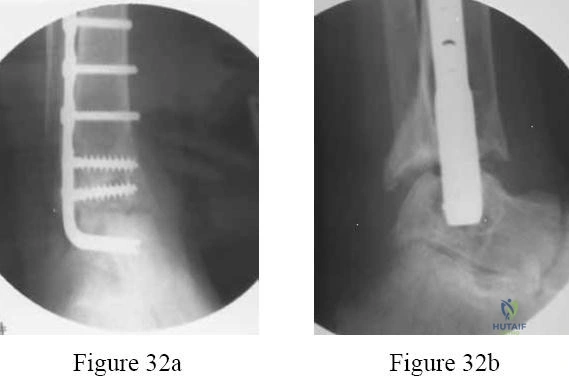

Question 32

A 60-year-old diabetic patient presents with a warm, swollen, erythematous left foot. Radiographs reveal fragmentation and periarticular debris around the midfoot, with subluxation of the tarsometatarsal joints. Skin is intact. Inflammatory markers are mildly elevated. What is the appropriate initial management?

Explanation